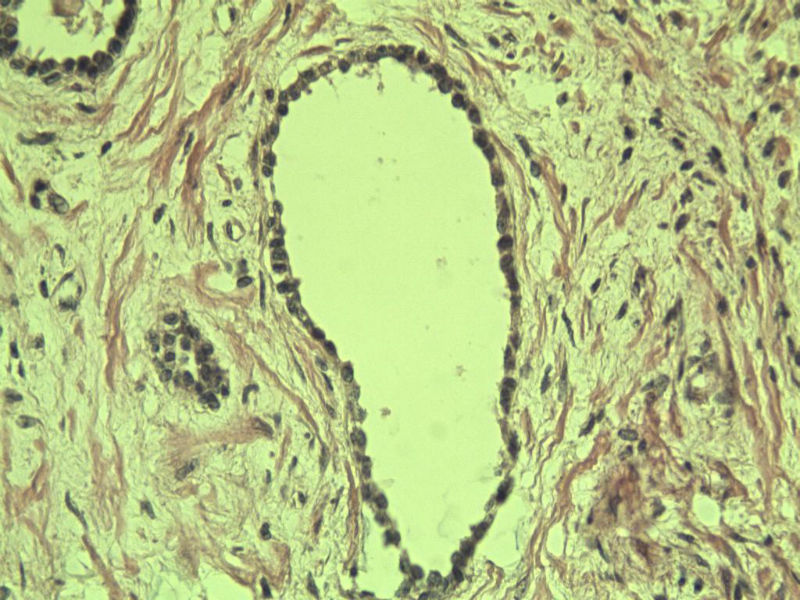

男 75岁 因排尿困难半年行前列腺切除术,体积 4 × 3 × 2.5 cm3,切面灰白,实性,质韧。请各位老师看看 有问题没? 谢谢了!

良性前列腺增生伴尿路上皮化生

呈巢上皮为尿道周围前列腺组织正常现象。尿路上皮-前列腺腺体过度。

前列腺增生症伴鳞化

良性前列腺增生伴brunnerr巢形成

前列腺增生,有腺瘤样结节形成。

前列腺增生伴尿路上皮鳞化及Brown巢形成,未见恶性。